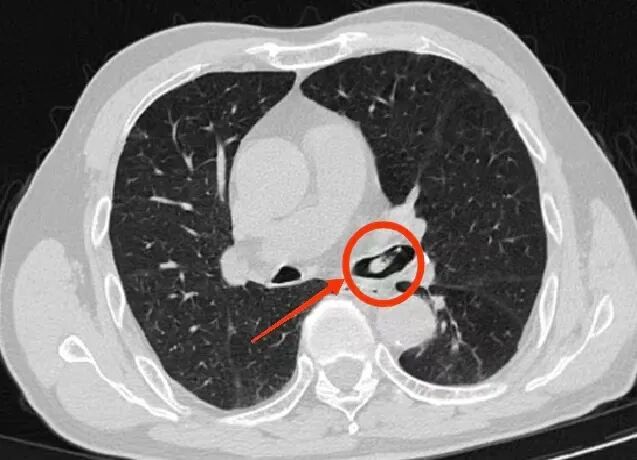

呼吸与危重症医学科副主任李涛立即安排支气管镜检查,在纤细的镜管探入下,只见那只虾顽固地嵌在支气管管口,周围黏膜已微微红肿。李涛屏息凝神,用微型钳子轻柔夹取至咽喉部,这只“误入歧途”的河虾经杨先生口中咳出。